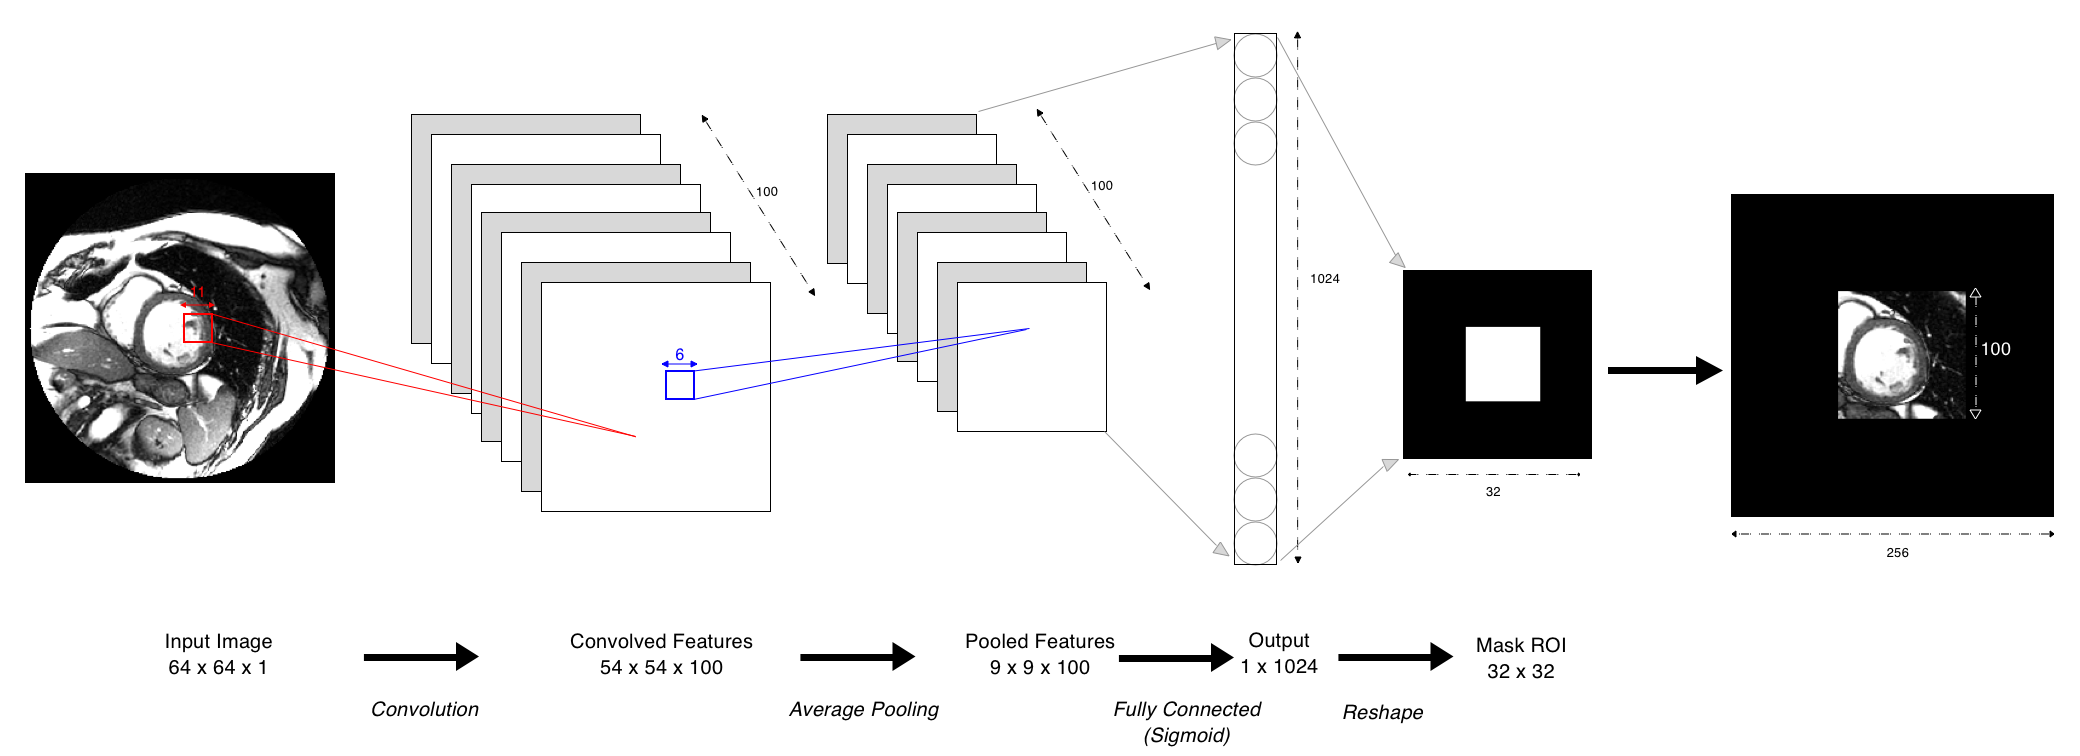

The CNN algorithm is represented in the block diagram Figure 3. As we can see, we only have one convolution layer, followed by a subsampling layer (Average pooling) and a fully connected one computing a logistic regression in order to assign a class to every pixel.

To build the convolution layer, we have 3 degrees of freedom regarding the filters. Indeed, using the notation for the output volume size, for the input volume size (64 in our case as we downsampled the image from to ), for the filter size, for the padding and for the stride,the following formula heps us choose our parameters :

As the LV is often the main part of the input image, we use large kernels (). The resulting convolved features map has the shape . The pooled features are unrolled from to before the fully connected layer (logistic regression) and then re-rolled to get the ROI binary mask (from to ). We use this binary mask to crop a ROI on the original MRI image.